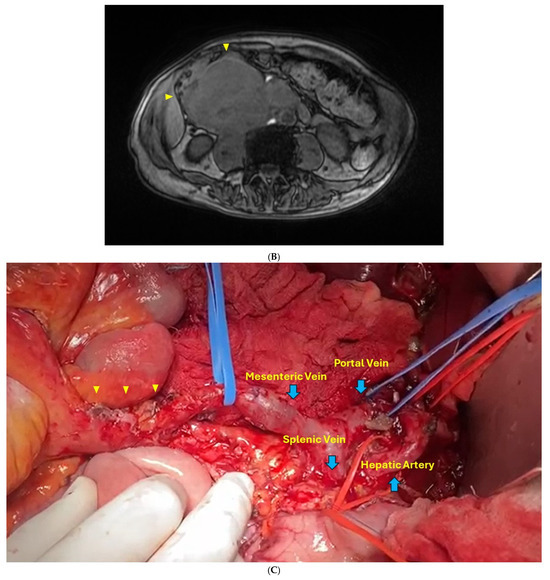

2.1. Case Report 1

2.2. Case Report 2